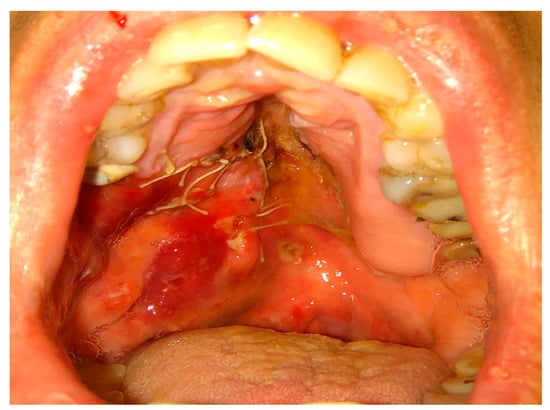

Figure 9. Adeno-carcinoma of the right palate after biopsy.

Figure 10. Modified Bichat fat pat and mucosal flaps advanced to cover the defect in the maxillary dental arch, lateral and medial bone wall, and hard palate after resection.

Figure 11. Result after 3 weeks. Notable residual sutures on the palate. A slight discolorization and scarring of BFP after advancement.